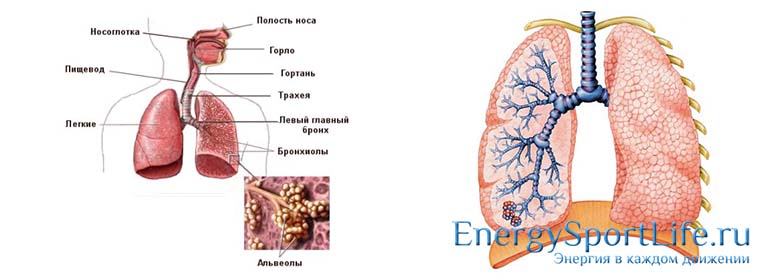

Дыхательная система

Для правильной жизнедеятельности человеку необходим кислород, который попадает в организм благодаря работе легких – основных органов дыхательной системы.

Дыхательная гимнастика для лёгких: профилактика заболеваний

Для того чтобы понимать, как работать с дыхательной системой, нужно иметь представление о её строении. Дыхательная система — органы и ткани организма, которые обеспечивают обмен газов между кровью человека и окружающей средой. Эта система включает в себя лёгкие и дыхательные пути.

Функция дыхания в анатомии человека

Система дыхания человека отвечает за насыщение организма молекулами кислорода, а также выведение отработанного углекислого газа и токсических соединений. По сути, это последовательно соединённые между собой трубки и полости, которые сначала заполняются вдыхаемым воздухом, а потом изгоняют изнутри углекислый газ.

Верхние дыхательные пути представлены носовой полостью, носоглоткой и гортанью. Там воздух согревается до комфортной температуры, позволяя предотвратить переохлаждение нижних отделов дыхательного комплекса. Кроме того, слизь носа увлажняет слишком сухие потоки и обволакивает плотные мельчайшие частички, которые могут травмировать чувствительную слизистую.

Нижние дыхательные пути начинаются гортанью, в которой не только осуществляется функция дыхания, но и формируется голос. При колебании голосовых связок гортани возникает звуковая волна, однако трансформируется в членораздельную речь она только в ротовой полости, с помощью языка, губ и мягкого нёба.

Далее воздушный поток проникает в трахею — трубку из двух десятков хрящевых полуколец, которая прилегает к пищеводу и впоследствии распадается на 2 отдельных бронха. Затем бронхи, впадающие в ткани лёгких, ветвятся на меньшие по размеру бронхиолы и т. д., вплоть до образования бронхиального дерева. Сама же лёгочная ткань, состоящая из альвеол, отвечает за газообмен — всасывание кислорода из бронхов и последующую отдачу углекислоты.